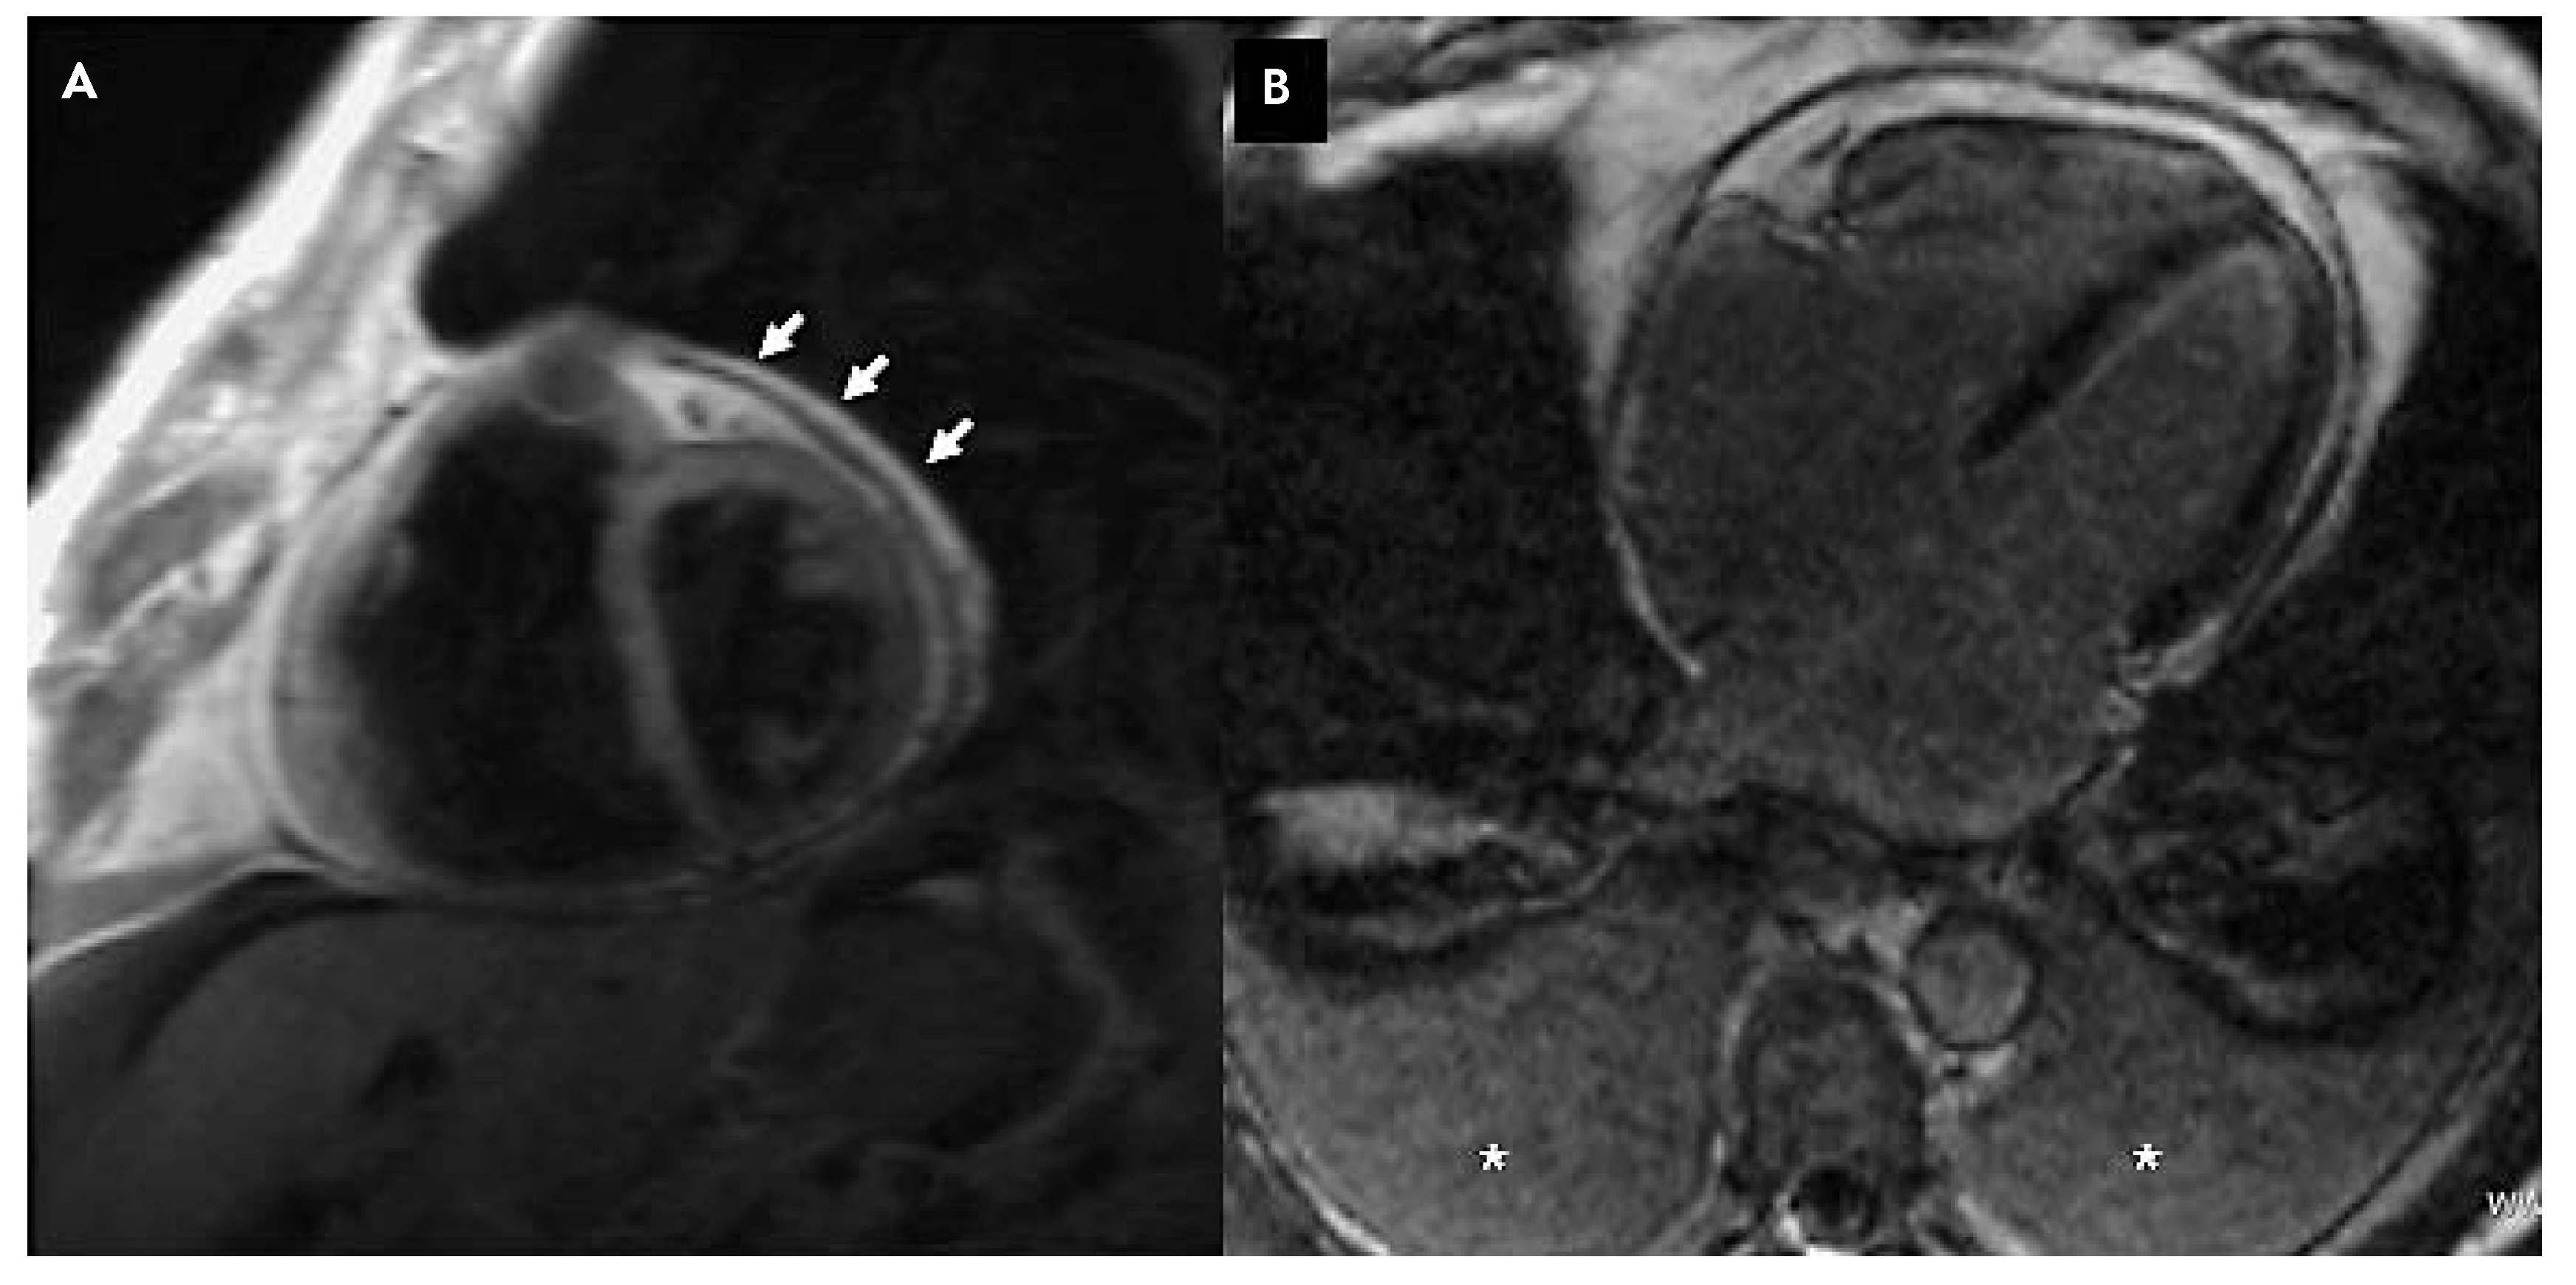

Due to poor echogenecity of the patient, cardiac MRI is performed and demonstrates: important pericardial thickening (6–7 mm) (Figure 3A), normal left ventricular function, interventricular interference during inspirium and a protodiastolic “septal bounce” (cine-MRI images). No late pericardium or myocardium enhancement is observed after Gadolinium injection (Figure 3B).

Figure 3. Cardiac MRI before and after gadolinium injection with late enhancement study. A T1 weighted sequences, short axis view, exhibiting flattening of the interventricular septum and pericardial thickening (arrows). B Late enhancement study after gadolinium injection showing absence of myocardial or pericardial enhancement confirming chronic pericarditis without acute inflammatory process (* denotes pleural effusions).